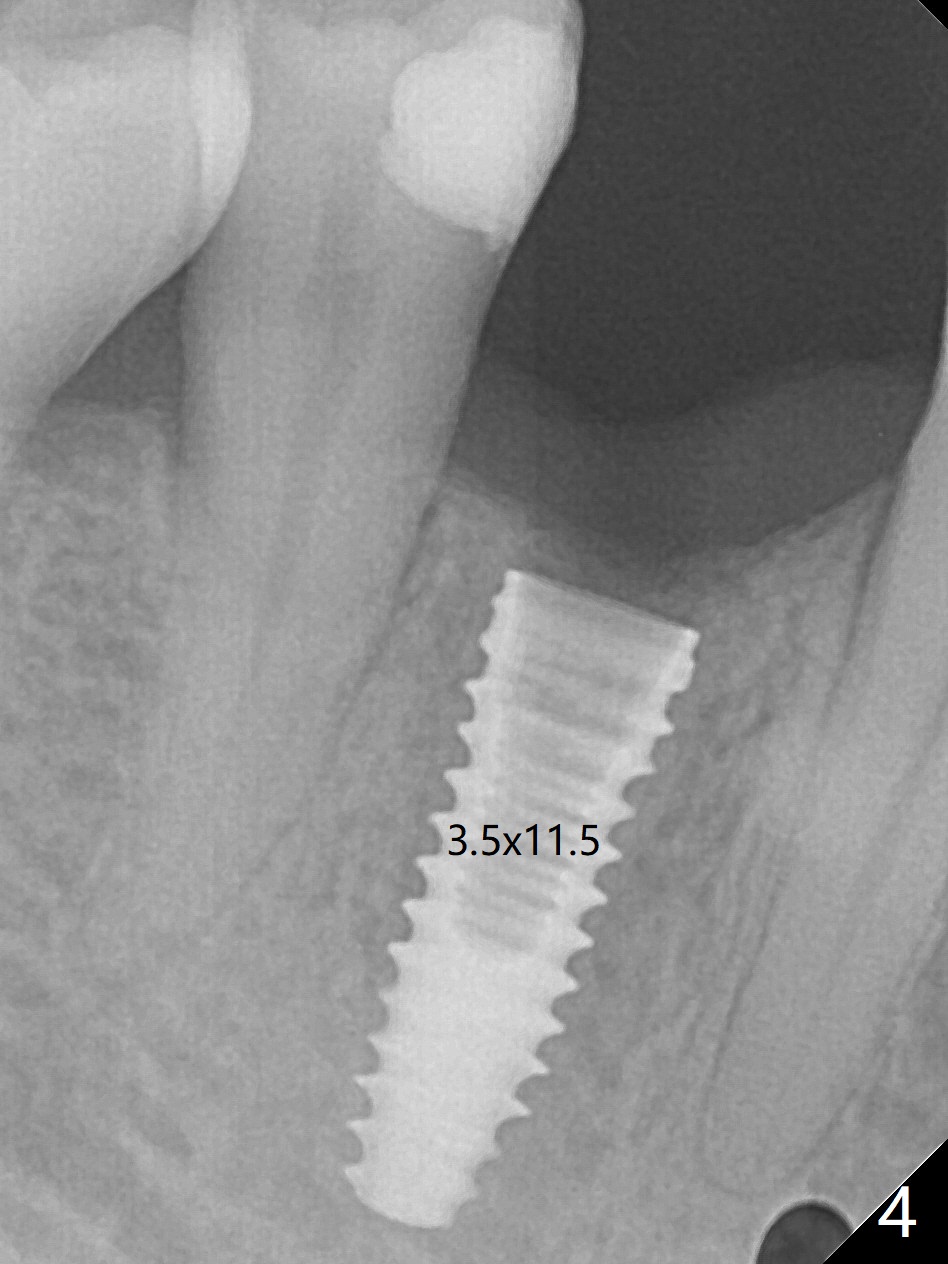

With 9 mm offset, the cylinder portion of the 2.2x8.5 mm drill does not engage to the metal sleeve of the guide at #28 after pointed drill (Fig.1). This issue could be solved with 12 mm offset, although it has no ill effect in this case. Fig.2 shows the site of #28 immediately before bone expansion and after use of 2.2x11.5 mm drill and small-scaled ridge split (^). The bone is so hard that the bone expansion is minimal (Fig.5) with autogenous bone graft and implant placement (Fig.4). There is the bone buccal to the implant clinically. A 5x10 mm implant is placed at #31 in the same appointment (Fig.3). Because of inability to masticate on the left (#18 root fracture with infection), the patient wants to restore #28 and 31 implants 3 months postop (Fig.6,7). The implant at #28 is removed while the healing abutment is being un-torqued without noting bone loss mesially (Fig.7 * (next similar case)). Bone graft is placed (Fig.8 (*),9). Pay attention radiolucency next the apex of the neighboring tooth (Fig.9 ?) before re-placement of an implant. The patient is upset, since he cannot eat. Two weeks later, a 6.5x4(4) mm cemented abutment is placed with 25 Ncm at #31 with a provisional for progressive loading for 2 weeks. Impression is taken. Two weeks later, a permanent crown is cemented without removing the underlying abutment. Two days later, the crown/abutment dislodges; a 6.8x6 mm healing abutment is placed. Eight days, it is difficult to reseat the existing crown and abutment. The mesiodistal edentulous space is limited as well. A 5.2x4(4) mm cemented abutment is able to be seated and torqued (30 Ncm) smoothly; in fact the clearance from the crestal bone (Fig.10 *) is not ample. If the abutment screw becomes loose in function, a profile drill should be used or a 4.5 mm in diameter abutment be placed. The abutment seems to remain in place immediate post cementation (Fig.11). Implant failure is probably due to no socket preservation (buccal plate atrophy) and too early restoration.